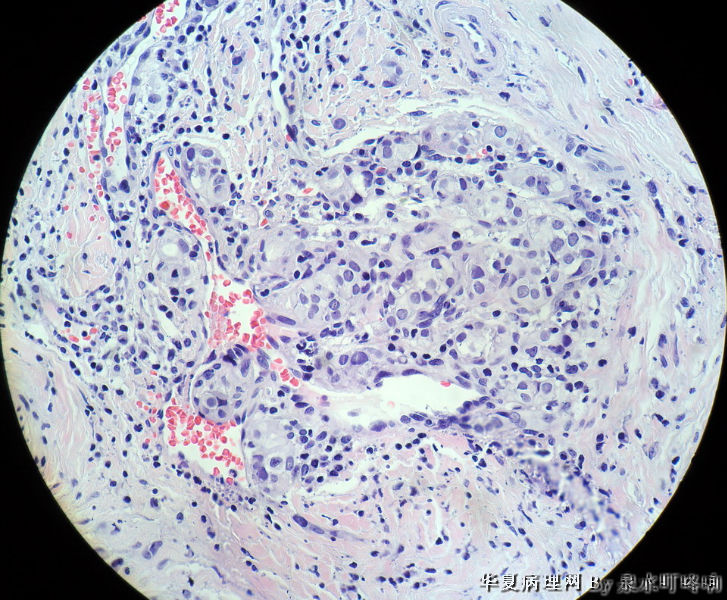

120212,女,55岁,左颈部肿物七年余。

大体:灰白肿物一个,大小约2.1×1.5×1.3厘米。表面光滑,包膜完整,切面灰白,部分包膜有钙化。

与手术医生沟通,肿物位于左颈部靠近甲状腺部位,比较浅(门诊手术),手术医生认为是淋巴结部位。

甲状腺滤泡状癌,有包膜浸润及血管内瘤栓

甲状腺滤泡性肿瘤,可见包膜及血管侵犯,考虑滤泡癌。

会诊结果:(颈左)考虑为甲状腺滤泡亚型乳头状癌,请结合临床进一步确认。